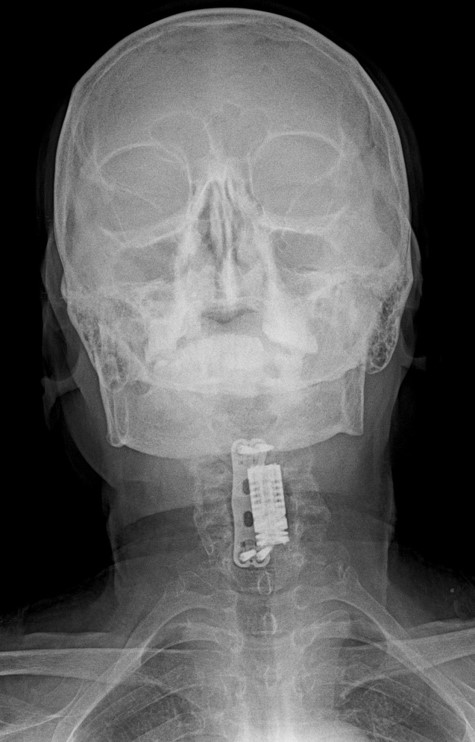

Ameliyat Sonrası